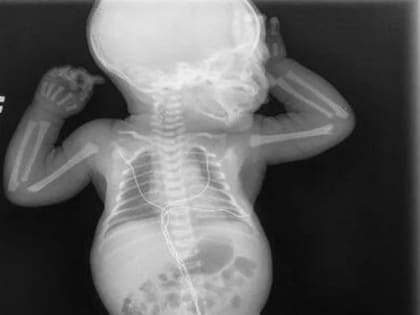

Подмосковные врачи спасли жизнь двум детям

Хирурги Московского областного центра охраны материнства и детства удалили новорожденному мальчику опухоль, составлявшую треть его веса.